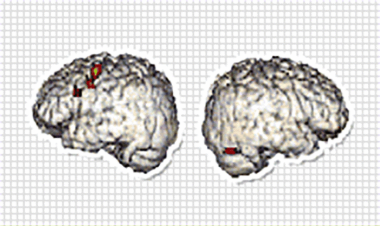

“妈妈,这道题怎么做?” “你自己上网查一下不就行了吗” 有没发现,不知不觉我们已经离不开手机了; 不管是在生活中,工作中,还是蹲坑中... 手机已经遍布了我们的生活,而有这样情况的还有我们的孩子; 当我们以为手机只是孩子课余的消遣,东北大学的川岛隆太教授研究团队用十年时间揭开了残酷真相 图源:网络 一、七万名学生的十年追踪 日本东北大学川岛隆太教授团队从2010年开始,对宫城县的七万名中小学生展开了长达十年的追踪调查。 当研究人员将每天屏幕使用时间超过1小时的学生成绩数据单独提取时,发现这些孩子的学业表现呈现出明显的下滑曲线。 图源:川岛隆太教授团队研究数据 更令人震惊的是,即便每天学习超过2小时的学生,只要手机使用时间超过3小时,其成绩居然不如几乎不读书但完全不碰手机的孩子。 这不是偶然现象。 ↑ 不节制玩手机情况下的大脑思考活跃度 ↑ ↑ 科学玩手机情况下的大脑思考活跃度 ↑ 研究团队每三年通过 MRI 对学生脑部进行扫描,发现长期沉迷手机的孩子,大脑中负责连接各功能区的白质神经纤维网络发育显著停滞。 这就像城市里的交通网络,如果主干道长期无法升级,整个城市的运转效率都会下降。 大脑的白质网络一旦发育迟缓,孩子的信息处理速度、专注力和逻辑思维能力都会受到根本性影响。 二、触目惊心的数据 这种现象并非日本独有。 美国弗吉尼亚大学的实验显示,即使手机处于关机状态放在桌上,也会使学生的专注力下降 20%,记忆测试得分降低 15%。 韩国延世大学的追踪研究更发现,手机依赖程度高的青少年,其大脑海马体体积比同龄人小 10%,而这个区域正是负责长期记忆形成的关键部位。 作为手机消费大国的中国,情况同样不容乐观。 2024 年数据显示,我国成年国民人均每天手机接触时长已达 108.76 分钟。 第22次全国国民阅读调查 当家长们在微信群里讨论孩子成绩时,或许没有意识到,那些在餐桌上、沙发上频繁亮起的手机屏幕,正在悄悄改变孩子大脑的神经突触连接方式。 三、说点心里话 小编在撰写这篇文章时,特别注意到一个细节: 川岛教授在建议中反复强调 "家庭成员应共同订立使用原则"。 这提醒我们,手机管理不是单方面的约束,而是全家共同的成长课题。 当父母在餐桌上放下手机,认真倾听孩子讲述学校趣事时; 当全家在周末开展 "断网日",一起在公园寻找春天的足迹时, 这些真实的情感联结才能帮助我们的孩子建立美好的生活。 参考文献